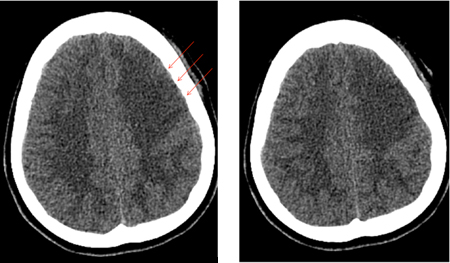

O vasoespasmo se desenvolve entre os dias 4 e 14 após a HSA e é observado na angiografia em 50% a 70% dos casos. Metade desses pacientes desenvolve deficits isquêmicos tardios (DIT) secundários à redução do fluxo sanguíneo cerebral (FSC) regional ou geral.[194] Se não tratado, o DIT evolui para um infarto cerebral permanente em 50% dos casos. Os deficits isquêmicos também podem ser observados na ausência de vasoespasmo angiográfico distinto. Acredita-se que isso se deva, em parte, à autorregulação alterada de vasos cerebrais distais, microtrombos em tais vasos e/ou despolarização de disseminação cortical.[195] Os fatores de risco para o DIT são mau estado geral no momento da admissão, quantidade e duração da exposição ao sangramento subaracnoide, acúmulos de sangue espesso nas cisternas e fissuras, sangue intraventricular e duração da ausência de consciência.[176][181][196][197][198] Embora a presença de sangue no espaço subaracnoide seja necessária para o desenvolvimento de vasoespasmo, a clipagem cirúrgica, durante a qual a maioria do sangue subaracnoide é lavado, parece não oferecer menos risco de vasoespasmo em relação à embolização endovascular com molas.[199][200][Figure caption and citation for the preceding image starts]: Vasoespasmo grave da artéria carótida interna esquerda distal e das artérias cerebrais média e anterior proximais antes (A) e depois (B) da infusão intra-arterial de nicardipino e da angioplastia transluminal com balãoCortesia do Dr. Salah Keyrouz; usado com permissão [Citation ends].

[Figure caption and citation for the preceding image starts]: Infarto frontal esquerdo (setas) em um paciente com vasoespasmo relacionado à hemorragia subaracnoideCortesia do Dr. Salah Keyrouz; usado com permissão [Citation ends].